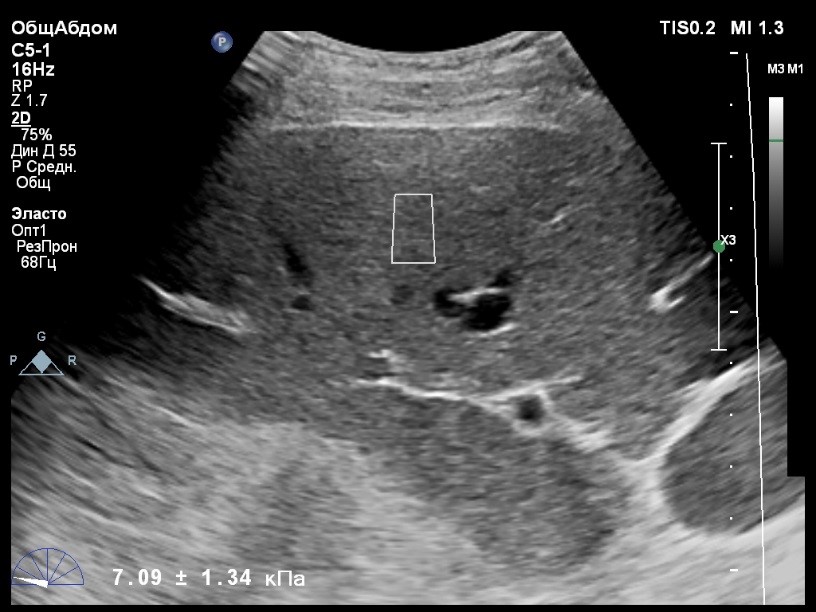

Пациент обратился к доктору с направлением на исследование степени жесткости печени в июне 2017 года. Из истории болезни, пациент страдает Гепатитом С с 2015 года. Лечение не получал. В апреле 2016 года, с помощью транзиентной эластографии была установлена медиана жесткости печени 5,8 kPA (4,4-7,7). На момент настоящего исследования, пациент не принимал пищу на протяжении 4 часов, АСТ, АЛТ не превышают патологических значений. Для оценки жесткости была выбрана технология компании Philips ElastPQ (точечная эластография) и прибор компании Philips Epiq 7 Исследование было проведено в соответствии с клиническими рекомендациями для ультразвуковых приборов компании Philips. В результате исследования были получены следующие результаты:

| 1 [4.94] kPa | 2 [7.09] kPa | 3 [7.13] kPa |

| 4 [4.74] kPa | 5 [5.17] kPa | 6 [7.78] kPa |

| 7 [6.19] kPa | 8 [7.63] kPa | 9 [4.64] kPa |

| 10 [6.18] kPa | 11 [4.49] kPa | 12 [4.54] kPa |

| 13 [6.08] kPa | | |

Стандартное Отклонение [1.17] kPa Медиана Жесткости [6.08] kPa Фактор Качества IQR/Med 9%

Зона интереса расположена на более чем на один сантиметр глубже капсулы, параллельно ходу луча, в середине изображения, в участке печени лишенном артефактов.

Капсула видна как белая линия перпендикулярная ходу ультразвукового луча, исследования производятся приблизительно в одном и том же сегменте печени.

Стандартное отклонение (0,96 kPA) не превышает 30 процентов от полученного значения (4,54 kPA).

Зона интереса расположена вне крупных сосудов.

Для интерпретации полученных клинических данных были использованы Рекомендации по проведению эластографии сдвиговой волной для оценки жесткости печени при использовании ультразвуковых аппаратов компании Филипс с примером протокола. Анамнез основного заболевания пациента достаточно короткий и показатели жесткости печени, полученные в 2016 свидетельствуют об отсутствии значимых фиброзных изменений. Однако, в течении всего времени пациент не получал специфического лечения. Данный факт является показанием для динамического наблюдения и оценки жесткости печени. Подготовка пациента соответствовала проводимому исследованию. Представленные слайды проведенного исследования свидетельствуют о правильном техническом исполнении проб, что позволяет заключиться о достоверности полученных измерений. Таким образом, учитывая полученную медиану жесткости на уровне 6.08 кРа (4.49 – 7.78 kPa) и уровень стандартных отклонений не превышающих 30%, полагаю, что уровень степени фиброза соответствует стадии F 0-1. Заведующий отделением УЗД МЦ «Асклепий», Глушенко Д. Е.